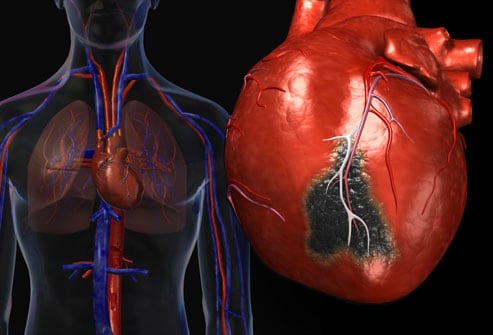

안정형과 불안정형을 나누는 가장 결정적인 차이는 어떻게 심장에 피의 공급이 줄었는가 이다. 안정형 협심증의 경우 신체적이나 심적인 스트레스가 있을경우 심장의 산소필요도 가 보통때 보다 증가했을때만 나타나는데, 보통은 관상 혈관에 아무 문제가 없기 때문에 산소 필요도가 증가할 경우 혈관 확장이나 심박수를 올려 심장에 피를 공급하는데 차질이 없다. 하지만 관상혈관이 막혀있을 경우엔 피의 공급이 심장의 산소 필요도를 따라가지 못해 흉통이 생기는것.

이와 다르게 불안정형 협심증은 외부 요인에 의하지 않았을때에도 관상 혈관이 이미 심각하게 막혀있으므로 심장에 최소한의 산소 필요도마저도 따라가지 못해 평상시에도 흉통이 생기는 증상이다. 불안정형 협심증은 흉통이 더 오래 지속되고 니트로글리세린으로도 완화되지 않는다. 진단은 위에 서술한것과 동일하게 진행되나, 심전도 검사시 ST Depression 이 보여진다.